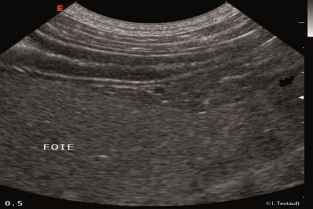

- réaliser un examen échographique de l’abdomen

- identifier les différents organes abdominaux et réaliser sur chacun les coupes standard

- reconnaître les différentes structures anatomiques normales.